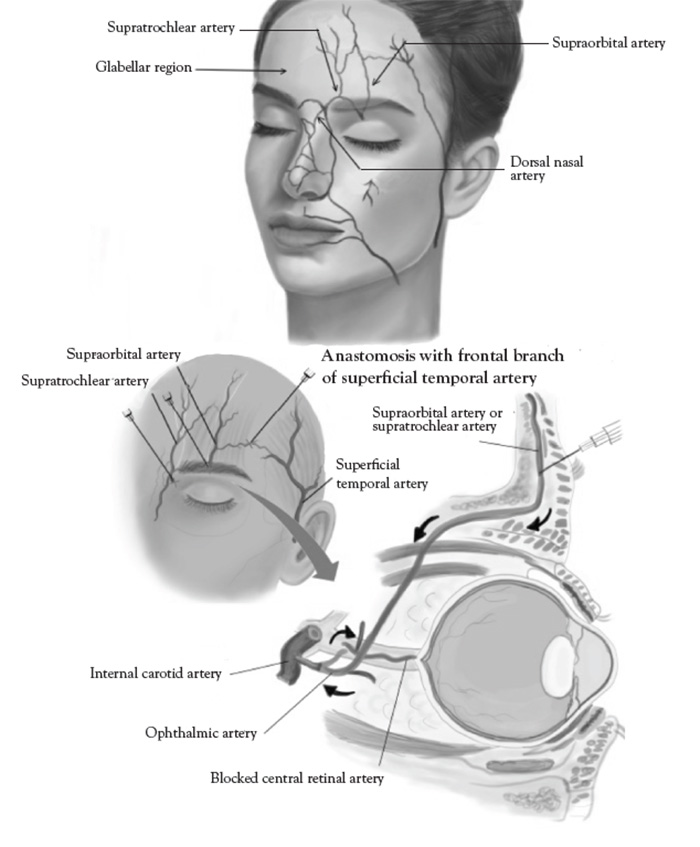

Vascular occlusion is a legitimate concern given the complex array of facial arterial anastomoses, asymmetry, and anatomic variation. Adverse outcomes appear related to the large number of cosmetic filler injections (more than 3 million procedures performed annually in the United States alone), and can be encountered even with experienced injectors. Most common complications are tissue ulceration, skin necrosis, and, rarely, blindness [120]. The FDA has issued a safety warning since 2015 [120]. The incidence of cosmetic filler related skin necrosis is 1:100,000 (or 0.001%). About 50% of complications occur in the glabellar region due to poor collateral circulation. The most common symptom of vascular occlusion is livedo reticularis, a netlike pattern of reddish-blue discoloration (occurring in 100% of patients), and decreased sensation (in 50% of patients). The most common sites of filler-related skin necrosis are the nose (33%) and nasolabial folds (30%). The most common site of filler-related blindness is the glabella (50%of cases) [121,122,123].

Aesthetic ultrasound is particularly useful in arterial mapping to identify potential "danger zones"of vascular occlusion and embolic complications. A discussion of relevant ultrasound-guided anatomic details is organized by zones in the upper, mid, and lower face, adapted from the current literature [129,130].

The superficial temporal artery is a branch of the external carotid artery and divides into frontal and parietal branches at the cranial portion of the zygomatic arch. The parietal branch is more medial and superficial to the temporal fascia, overlying the temporalis muscle, and must be avoided [131]. Inadvertent direct injection and/or compressive ischemia can cause retrograde embolization of the ophthalmic artery and blindness [132]. The superficial temporal artery must be carefully palpated and marked; cannula placement should be medial when placing polydioxanone (PDO) threads for midface lifts. The superficial temporal artery is visible with color Doppler ultrasound, when performed with proper technique (Figure 6).

The supratrochlear artery and branches are highly vascular and supplies the glabellar region. Inadvertent direct injection and/or compressive ischemia can cause retrograde embolization of the ophthalmic artery, blindness, and glabellar skin necrosis [135]. The glabella is the most common filler injection site leading to blindness [136]. Techniques for correcting deep rhytids in the glabellar region should include small intradermal microinjections and avoiding over filling [137]. The supratrochear artery is too small in caliber and not amenable to conventional color Doppler ultrasound not otherwise equipped with power Doppler capability.

The paranasal area becomes a target in aesthetic practice, particularly with regard to injection of cosmetic fillers in achieving a "liquid rhinoplasty" or nasal contouring (Figure 7).Unlike other areas of cosmetic filler injections, midline nasal injections should be injected deep rather than superficial, because vascularity is more superficial, avoiding nasal bridge and ala [139]. Safe zones include midline middle third and lateral zone between the borders of the lateral nose and nasofacial groove. Avoid superficial injections of the alar tip and alar groove (avoid the crease) [139]. Nasal injection is the leading cause of tissue necrosis (Figure 8) [139,140].